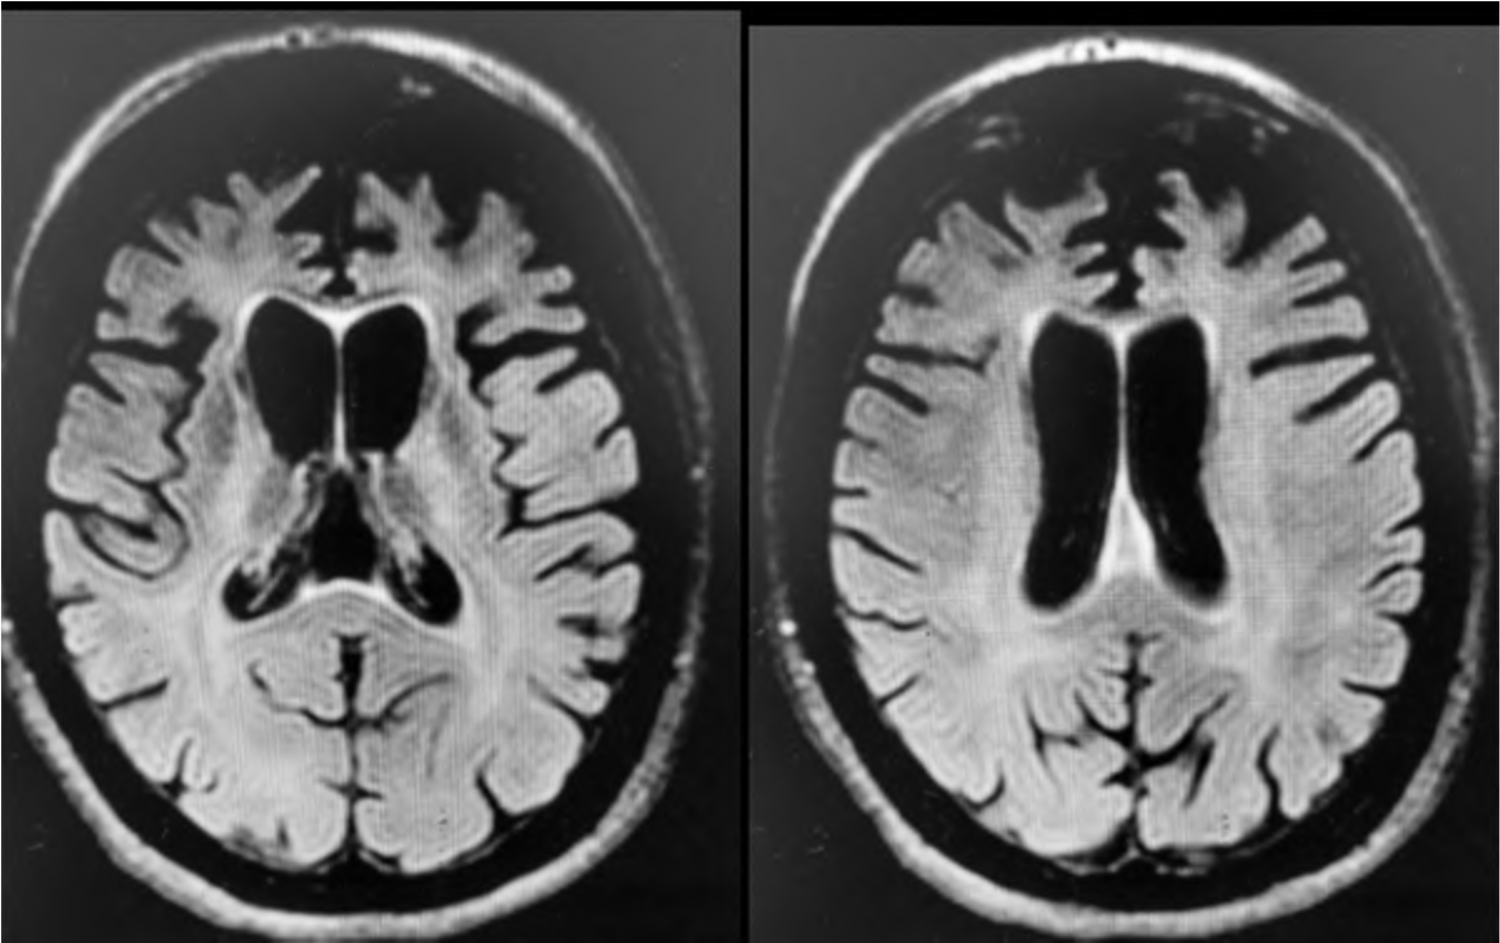

F.E.A, 64 anos, casada, superior completo, professora do ensino fundamental. Segundo os familiares, até 5 anos atrás a paciente tinha funcionalidade preservada, bom rendimento no trabalho, frequentava a igreja e atividades sociais. Nesses 5 anos começou a ficar mais retraída, reduziu contato social e permanecia mais em casa. Inicialmente pensaram que essas alterações estavam relacionadas à aposentadoria, mas com o passar do tempo começou a recusar ver filhos e netos, além de apresentar comportamento mais desinibido, sem prejuízo da necessidade de sono ou aceleração psíquica. Na avaliação clínica, verificou-se prejuízo visuoespacial e de função executiva significativos, associados a comprometimento da cognição social e pensamento lógico. Memória relativamente preservada. Funcionalidade prejudicada, com declínio das atividades instrumentais de vida diária. Ao exame físico, apresentava regular estado geral, algo descuidada, sinais vitais dentro dos parâmetros de normalidade. O exame neurológico apresentou grasping positivo, sem outras alterações. Exames gerais, EEG e líquor dentro dos parâmetros de normalidade. O exame de ressonância do crânio revelou a seguinte imagem:

Considerando os sintomas descritos, o diagnóstico diferencial mais provável a ser feito pelo psiquiatra é: